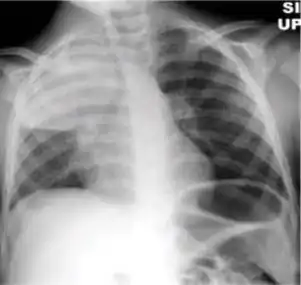

Chest X-ray of a person with advanced tuberculosis: Infection in both lungs is marked by white arrow-heads, and the formation of a cavity is marked by black arrows.